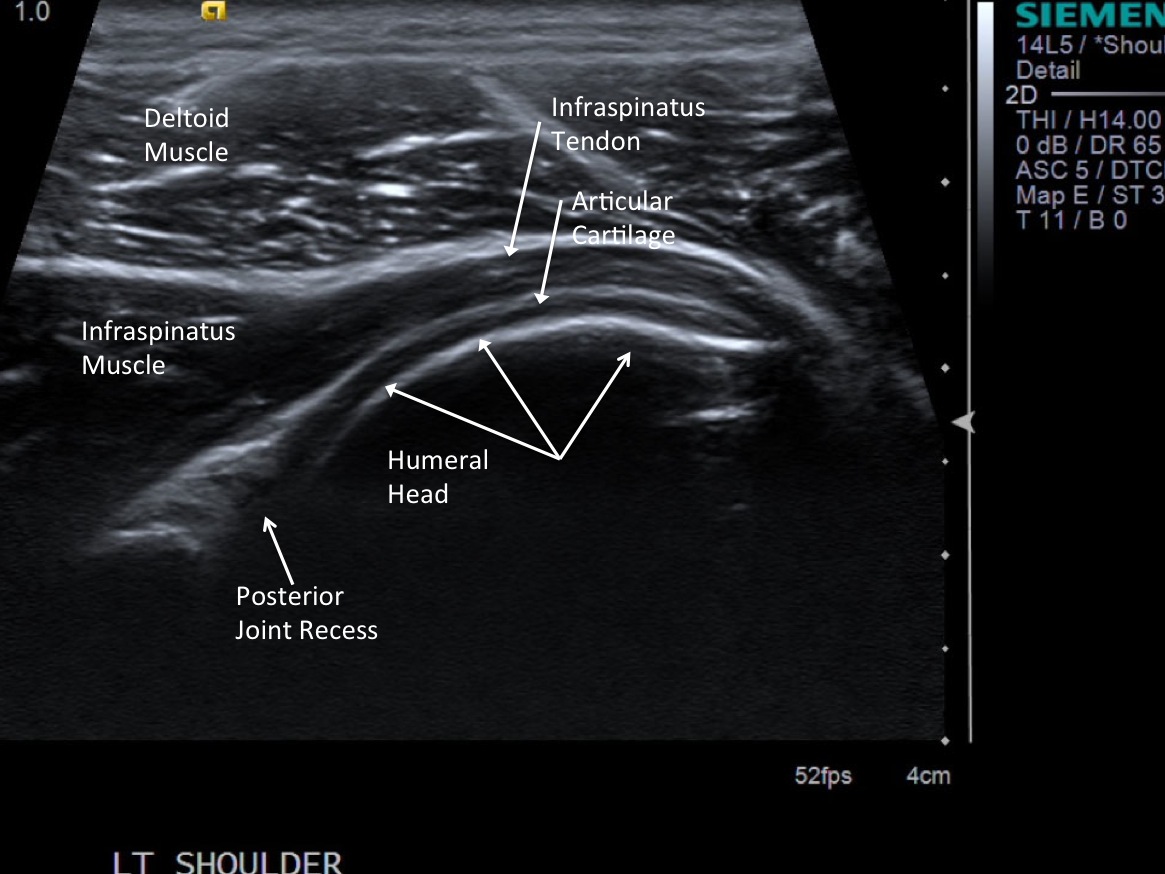

3. Scan patient looking for the posterior glenohumeral joint space. Image at the level of the infraspinatus tendon insertion in longitudinal orientation. Position probe so you can inject from anterior.

• descriptiondescription

• After advancing the needle to the level of the articular cartilage, there is easy flow of the injectate.

13. Document distention of the posterior joint recess with ultrasound.